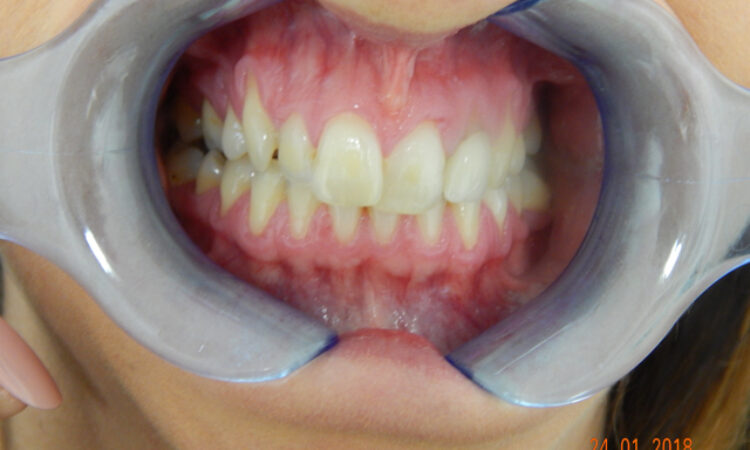

Before - puredental After - puredental

Case 17 - Invisalign®